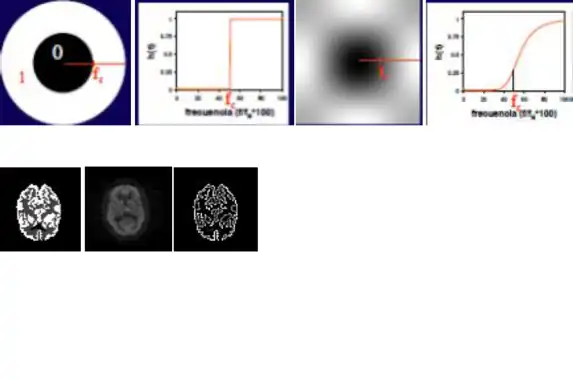

El filtrado las imágenes médicas, en este caso las imágenes de medicina nuclear, pueden asemejar a los filtros paso de banda, debido al estudio de las imágenes en el espacio de las frecuencias (espacio de Fourier).

Los cambios bruscos de intensidad y los detalles finos van asociados a componentes de alta frecuencia, de modo que si se eliminan estos componentes, la imagen resultante que se obtiene a partir de la transformada de Fourier inversa carece de estos detalles finos.

Filtros paso-baja

Este filtro efectúa un filtrado paso-baja cuyo grado de filtrado se controla por el radio del círculo. Un filtro muy abrupto puede producir oscilaciones en la imagen (fenómeno de Gibbs) por lo que suelen emplearse filtros paso-baja como el indicado a la derecha, que tienen una variación más suave. Son filtros con valores altos en el origen y que se atenúan hacia altas frecuencias.

Un filtro paso-baja puede implementarse también en el dominio espacial mediante convolución con una máscara de filtrado. La implementación de este filtro en el dominio espacial presenta ventajas en tiempo de cálculo frente a una implementación en el dominio frecuencial. Como regla general, si la respuesta impulsional del filtro es de tamaño menor que 12x12 píxels, el filtrado es mejor realizarlo en el dominio especial.

El radio del círculo, que determina el grado de filtrado, se expresa como fracción de la frecuencia de Nysquist.

Filtro paso-alta

La implementación de un filtro paso-alta puede realizarse en el espacio de Fourier, con un planteamiento complementario al del filtro paso-baja.

El efecto de este filtro, que actúa por multiplicación en el espacio de Fourier será, pues, de potenciación de la alta frecuencia y eliminación de la baja frecuencia. Son filtros de realce o de extracción de contornos.

Un filtro paso-alta puede implementarse también por convolución en el dominio espacial.

Un ejemplo de filtro paso de alta es el filtro laplaciano, el cual es omnidireccional y extrae contornos en todas direcciones.

Con este tipo de filtros, la detección del contorno es perfecta en las imágenes sintéticas sin ruido, pero en la imagen con ruido del estudio real, el filtro no sólo no detecta el contorno sino que potencia el ruido. Este refuerzo del ruido es una característica de los filtros paso-alta.

El grado de filtrado se controla con el radio del círculo interior, que controla la frecuencia de corte.